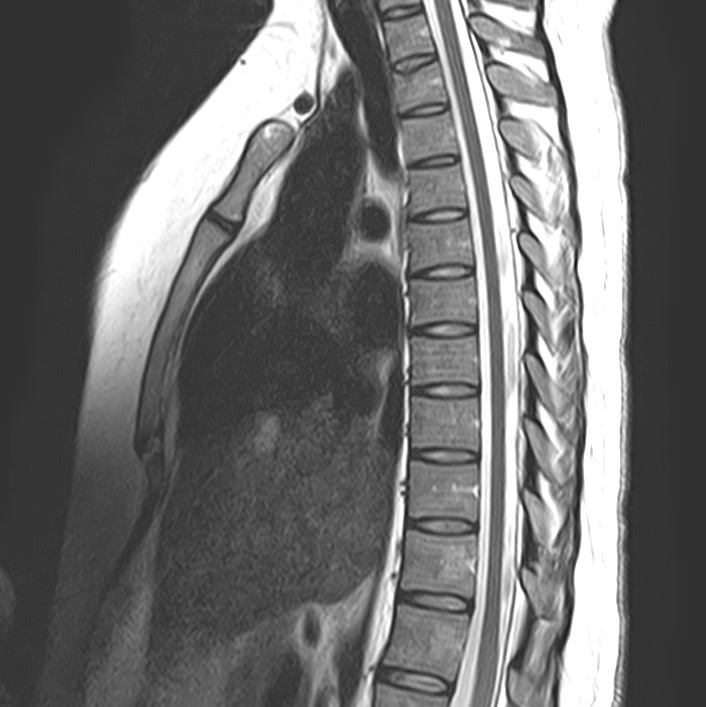

МРТ является современным высокоточным исследованием грудного отдела позвоночника, с помощью которого можно диагностировать различные заболевания, в том числе воспалительные, дегенеративные и опухолевые процессы. Преимуществом данного метода является его безопасность (отсутствие рентгеновского излучения), безболезненность, неинвазивность, при этом высокая информативность.

Клиника «Доступная медицина» оснащена новейшим томографом экспертного класса TOSHIBA VANTAGE TITAN 1,5 Тесла, который позволяет получать превосходные изображения с мельчайшей детализацией всех структур исследуемой области. Это позволяет ставить точный диагноз и выявлять различные заболевания позвоночника на самой ранней стадии.

С помощью МРТ грудного отдела выявляют следующие заболевания позвоночника:

• новообразования;

• степень повреждения спинного мозга в случае переломов тел позвонков;

• грыжи Шморля;

• травматические повреждения тел позвонков и остистых отростков (трещины, переломы, смещения и пр.) — при недоступности КТ;

• разрывы, растяжения связок;

• травмы спинного мозга, нервных корешков;

• протрузии;

• грыжи межпозвонковых дисков;

• остеохондроз позвоночника;

• стеноз спинномозгового канала;

• сосудистые патологии;

• остеомиелит, спондилодисцит;

• рассеянный склероз;

• спондилоартроз;

• спондилез.